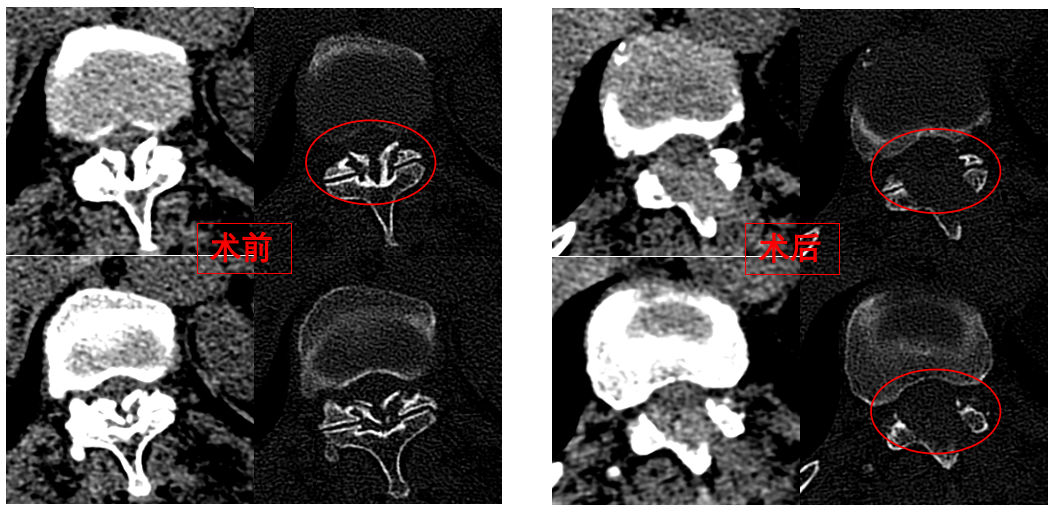

華西醫(yī)院成辦分院骨科副主任醫(yī)師張斌接診后,憑借豐富的脊柱治療經(jīng)驗(yàn),立即安排卓瑪阿媽做了系列精密檢查,檢查結(jié)果顯示,阿媽胸椎11/12節(jié)段黃韌帶嚴(yán)重骨化,導(dǎo)致椎管顯著狹窄,脊髓受壓,確診為嚴(yán)重的“胸椎黃韌帶骨化癥”,如果不及時(shí)手術(shù)最終可能面臨癱瘓的風(fēng)險(xiǎn)。

手術(shù)歷時(shí)一個(gè)半小時(shí),骨科脊柱微創(chuàng)團(tuán)隊(duì)成功完整切除了壓迫脊髓的骨化黃韌帶,徹底解除了卓瑪阿媽的脊髓壓迫。手術(shù)過程順利,手術(shù)切口僅1厘米。

圖為卓瑪阿媽術(shù)前、術(shù)后胸椎CT照片對(duì)比。